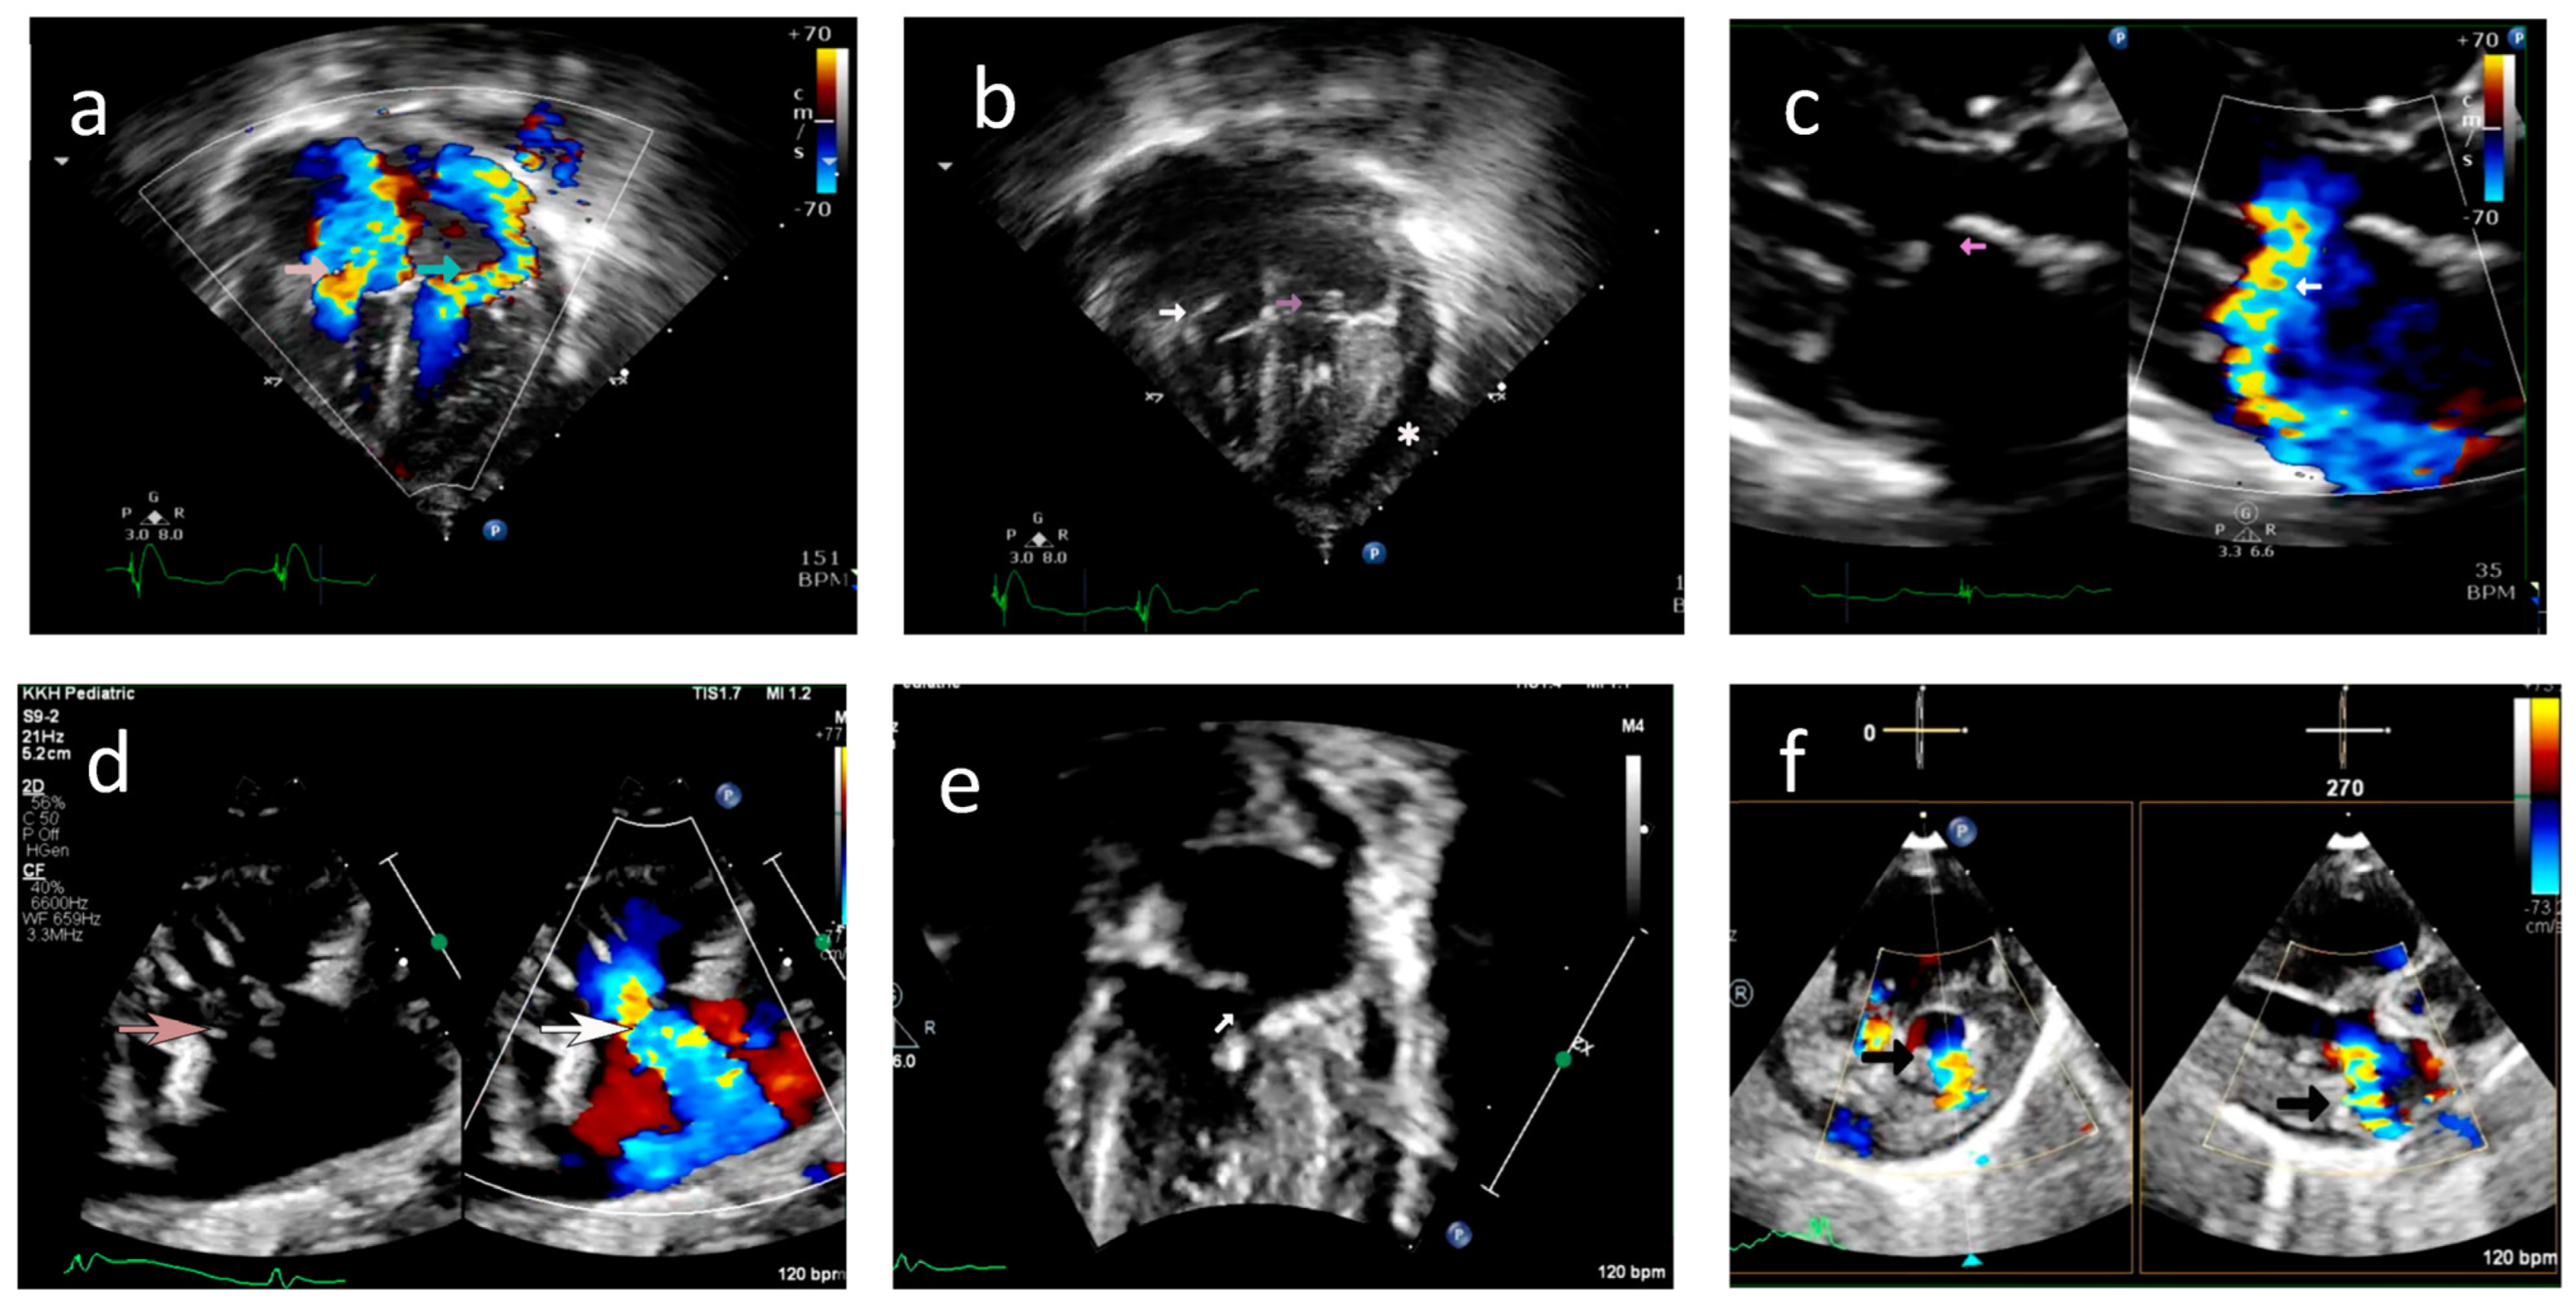

A 35-year-old G2P1 with no prior history of autoimmune disease was referred to our center at 20 + 4 weeks of gestation for fetal hydrops and bradycardia. CHB was detected in fetal echocardiography with an atrial rate of 112 bpm and a ventricular rate of 62 bpm (Figure 5a). Mild to moderate TR was present without MR. Biventricular hyperechogenicity of the papillary muscles and endocardium was noted with good coaptation of the valve leaflets (Figure 5b/Video S12). Small pericardial and pleural effusions were also noted. She was extensively investigated for hydrops, and her anti-Ro antibody titers were strongly positive with negative anti-La titers. She declined medical therapy and had her pregnancy terminated.

Figure 5.

Case B: (a) M-mode echocardiogram showing atrioventricular dissociation in the fetus. A—atrial contractions; V—ventricular contractions. (b) Echocardiogram, four-chamber view—hyperechoic papillary muscle (white arrow in RV and LV).

Case A: A cardiac postmortem showed the tricuspid valve (TV) had an abnormally small shrunken anterior leaflet with ruptured papillary muscles. The mitral valve (MV) is abnormal with dysplasia of the central portion of the anterior leaflet without the chordal attachments (Figure 6a,b). The surfaces of the myocardium and the pericardium were normal.

Figure 6.

(a) Case A—postmortem gross morphology: mitral valve with ruptured chordae of the anterior leaflet of the mitral valve resulting in shrunken leaflets (black arrow). Calcified chordae (blue arrow). (b) Case A—postmortem gross morphology: mitral valve with retraction and loss of leaflet tissue (black arrow). Calcified/fibrotic chordae (brown arrow). (c) Case B—postmortem gross morphology: left ventricle showing normal mitral valve leaflets (*). Fibrotic/calcified chordae and papillary muscle tips (black arrows).

Case B: Pale appearance of the tips of papillary muscles over both the MV and TV without chordal rupture (Figure 6c).

Case A: The histopathological examination of the cardiac tissue in Case A demonstrated calcification of the tip of the papillary muscle extending into the chordae tendineae (Figure 7a). There was rupture of the chordae of the posterior papilla with the myxoid change in MV. The atrioventricular node showed extensive calcification and fibrosis (Figure 7b). There was diffuse subepicardial calcification along with the right ventricular endocardium without fibrosis and subpericardial left ventricular calcification (Figure 7c). Normal coronary arteries were present without any signs of vasculitis (Figure 7d). Postmortem findings did not show active inflammatory cells or signs of prematurity in the lungs, liver, or brain.

Figure 7.

Case A: (a) Hematoxylin and eosin-stained section (original magnification 4×) of the left ventricular papillary muscle with calcified tip (green arrow). *—ruptured chordae showing fibrosis. (b) Hematoxylin and eosin-stained section (original magnification 10×) of the atrioventricular node area with calcification (green arrow) and fibrosis (*). (c) Hematoxylin and eosin-stained section (original magnification 20×) of the myocardium (black arrow) and pericardium (light blue arrow) showing extensive subpericardial calcification (green arrow) extending to the myocardium. (d) Hematoxylin and eosin-stained section (original magnification 10×) of the coronary artery (black arrow), which showed no inflammation.

Case B: The histopathological examination of the cardiac tissue showed extensive calcification and fibrosis with hypercellularity of the atrioventricular node and papillary muscles (Figure 8). Similar changes were also noted in the subendocardial portions of the left ventricle (LV) and the epicardial regions of the right ventricle (RV). Granulation tissue with multinuclear giant cells with calcification and fibrosis in the atrioventricular node and papillary muscle extending to the myocardium were observed (Figure 8).

Figure 8.

Case B: (a) Hematoxylin and eosin-stained section of the atrioventricular node (original magnification 10×)—calcification (black arrow), fibrosis (*), granulation tissue with neovascularization (red arrow). (b) Hematoxylin and eosin-stained section (original magnification 10×) of the atrioventricular node—acute inflammatory changes with granulation tissue (*), multinucleated giant cell (black arrow). (c) Hematoxylin and eosin-stained section (original magnification 4×) of the right ventricular papillary muscle with chordae. (d) Hematoxylin and eosin-stained section (original magnification 10×) of the right ventricular papillary muscle with chordae, fibrosis (green arrow), and calcification (black arrow).